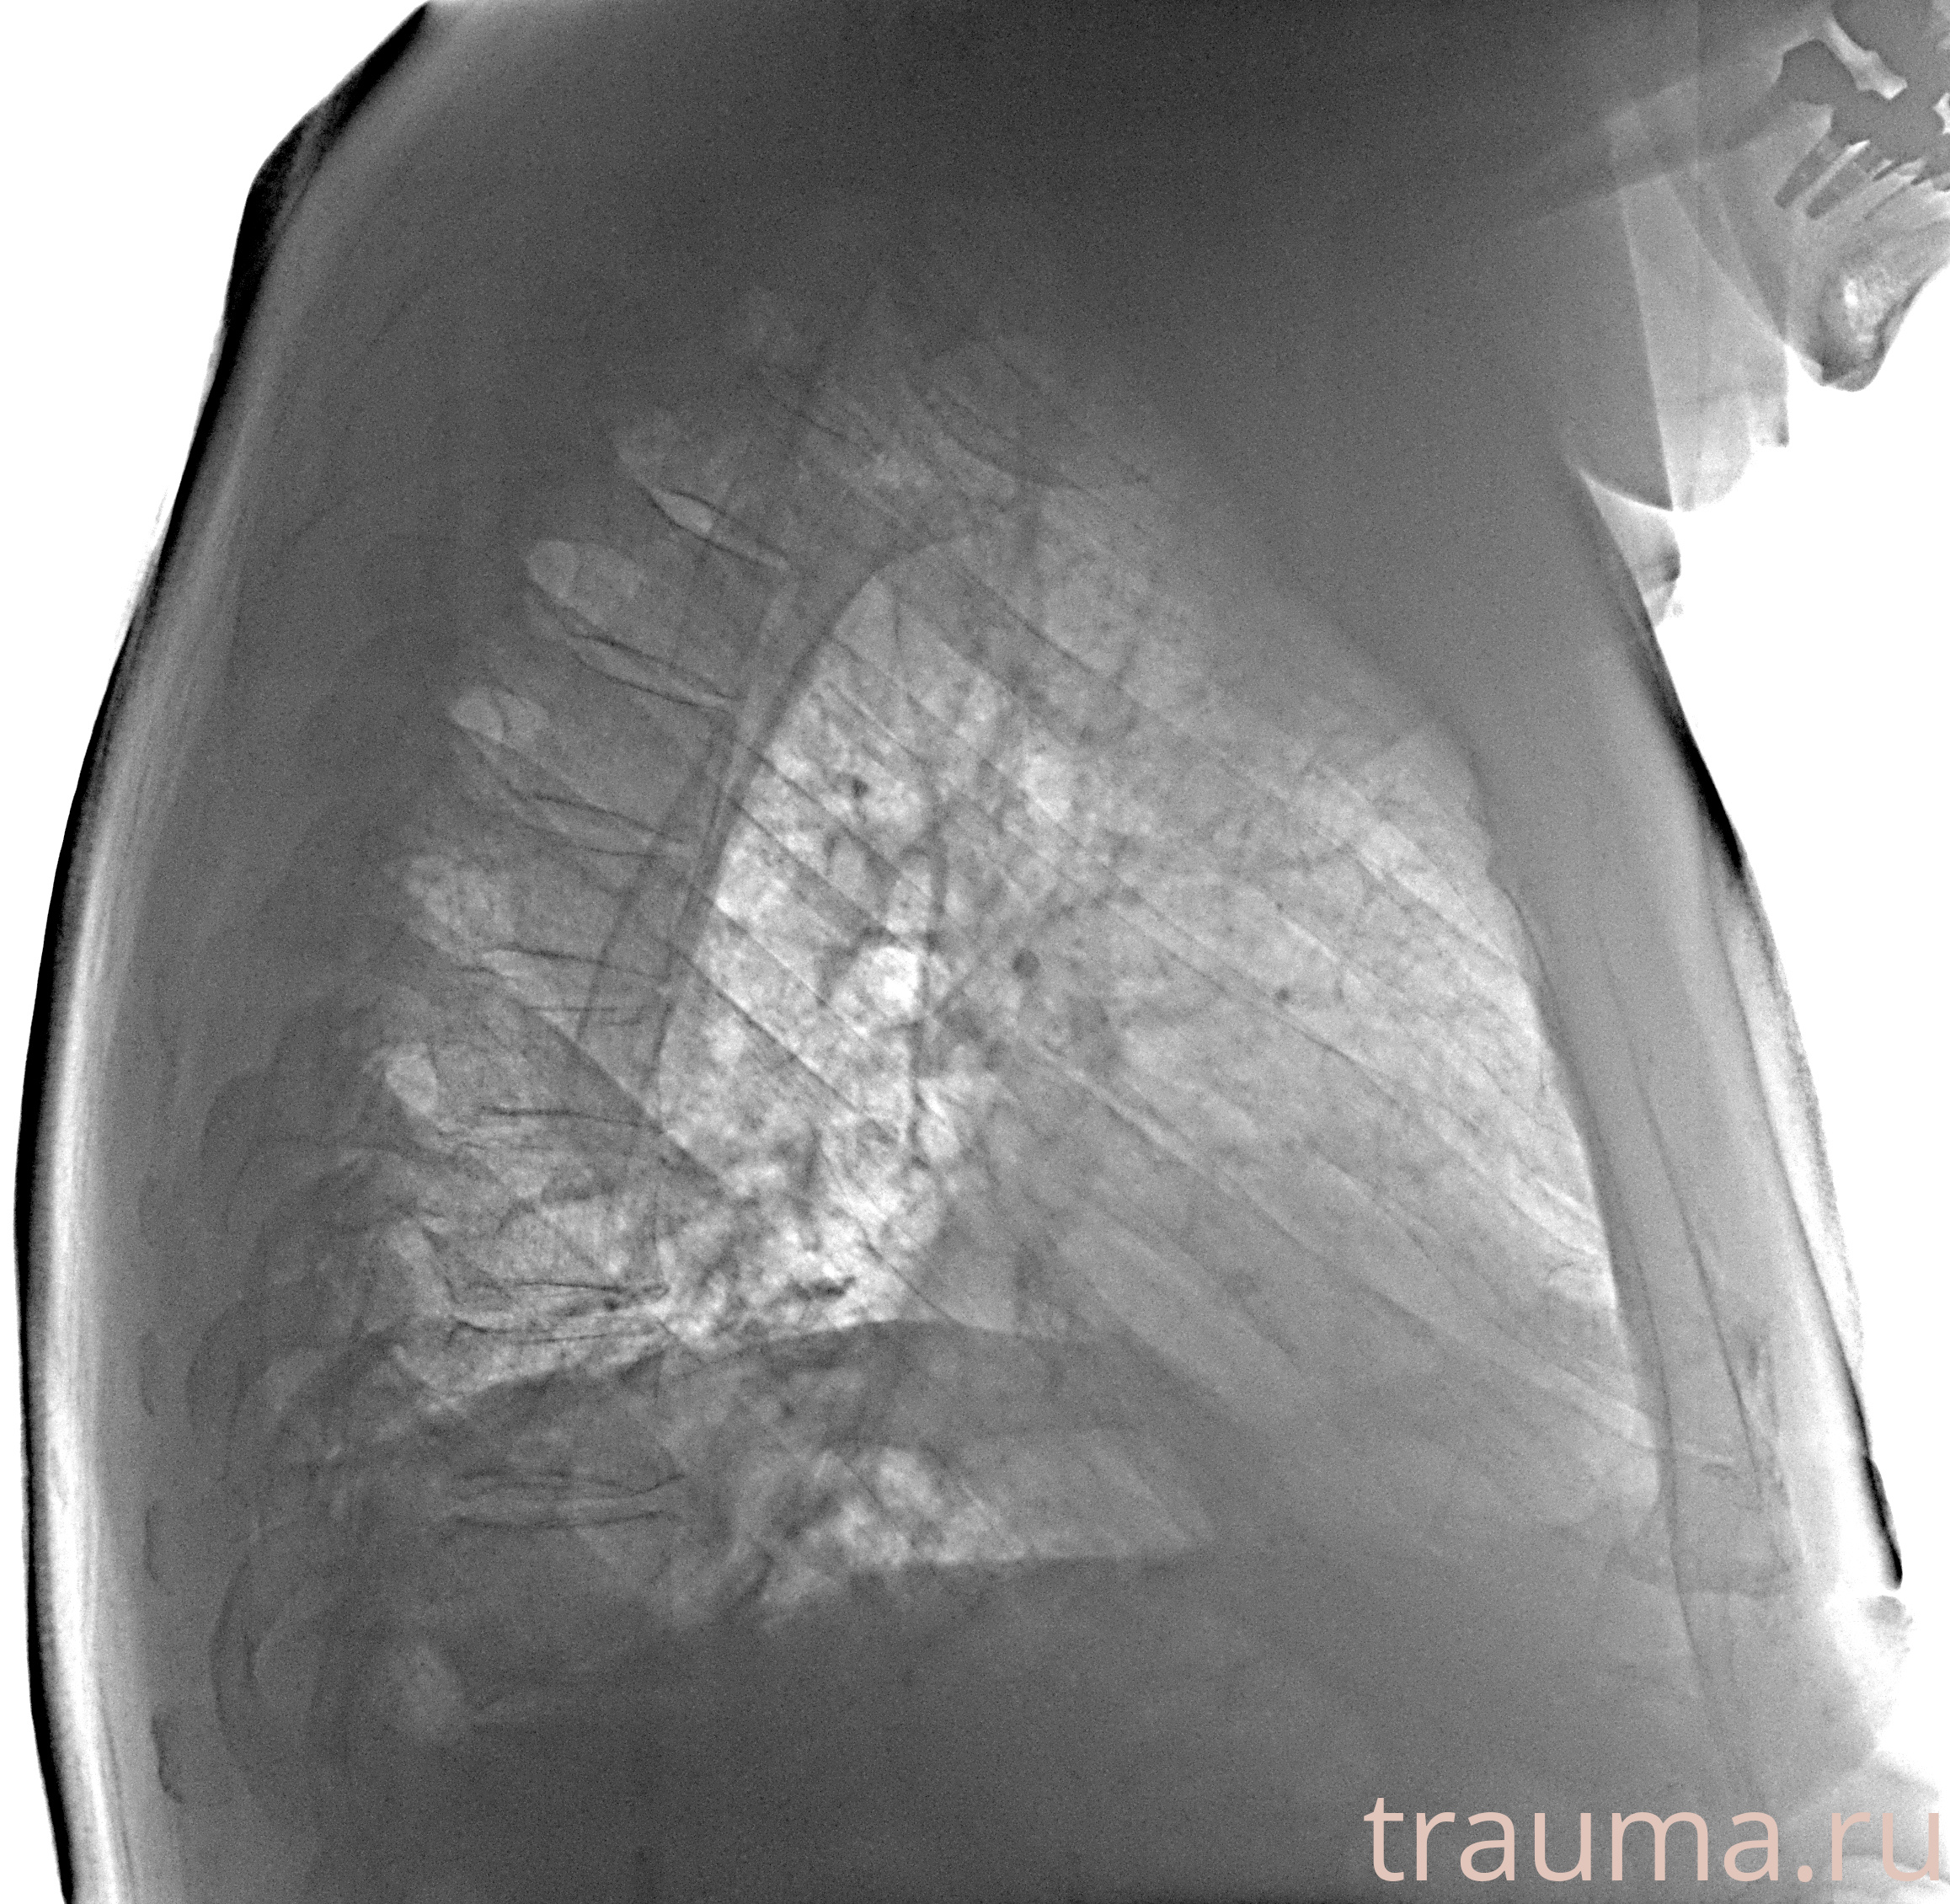

Рентген на дому: по вашему адресу приезжает врач-рентгенолог, травматолог-ортопед с мобильным рентгеновским аппаратом, проводит диагностику травмы или заболевания, делает необходимые рентгенограммы, дает рекомендации по дальнейшему лечению. Получить качественные снимки в домашних условиях возможно благодаря уникальной методике, разработанной МосРентген Центром для института  Склифосовского